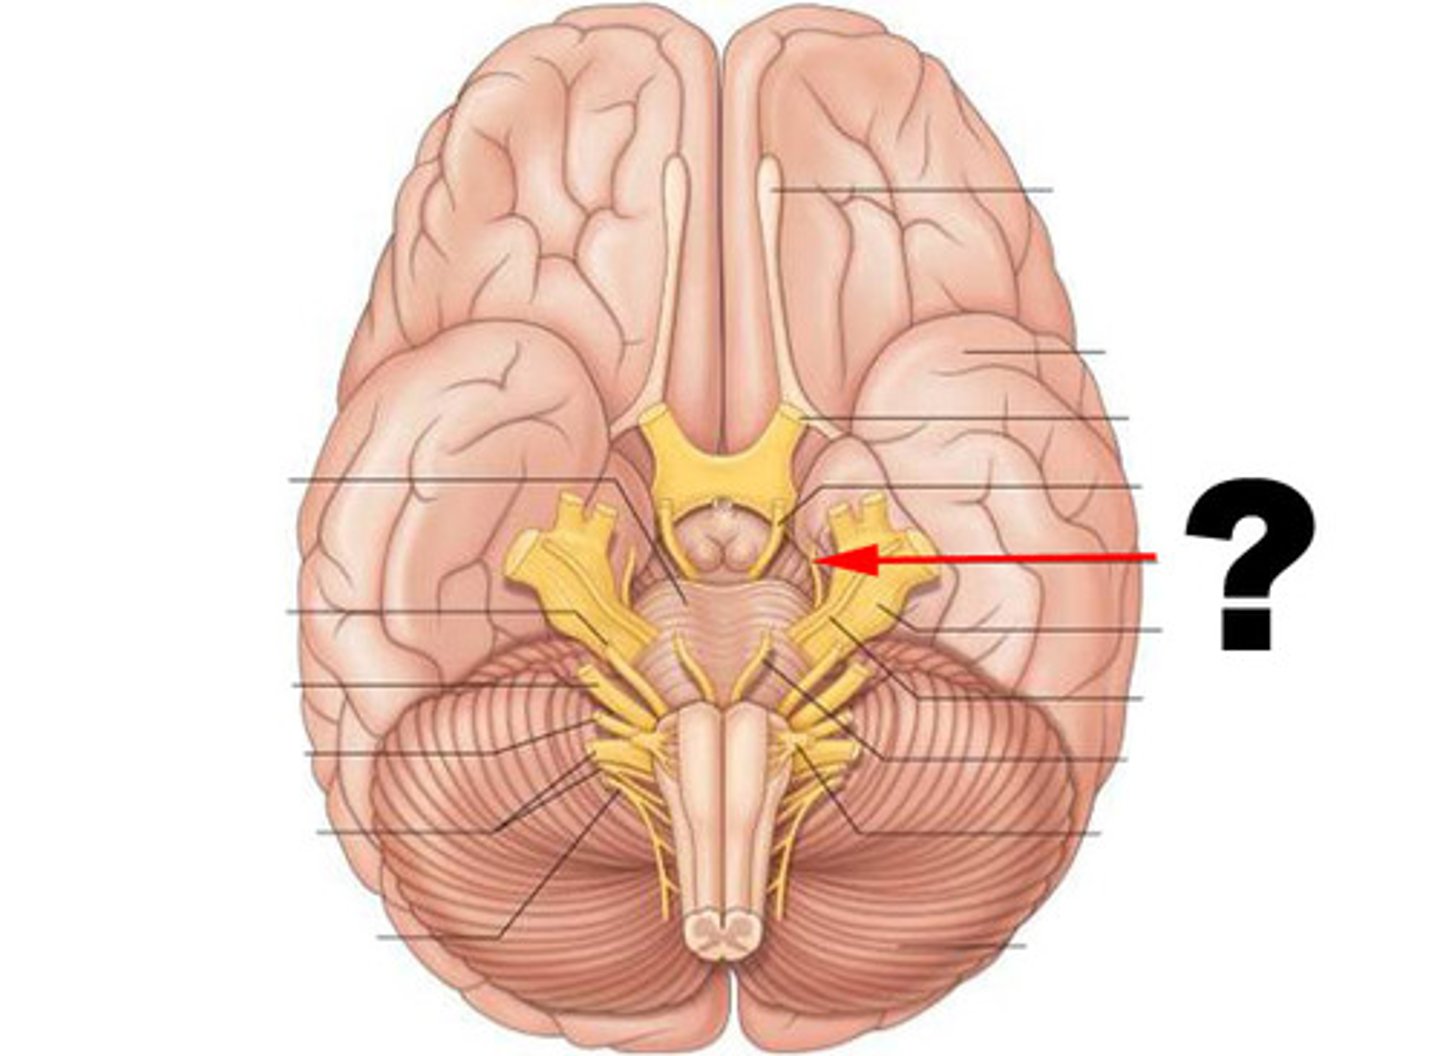

oculomotor nerve (CN III)

Motor cranial nerve that innervates extraocular and intraocular muscles involved in eye movement (up, down, medial), eyelid elevation, and pupil constriction; involved in direct light reflex, consensual light reflex, and accommodation reflex

trochlear nerve (CN IV)

Motor cranial nerve that controls movement of the eye inferiorly and laterally; innervates superior oblique muscle

abducens nerve (CN VI)

Motor cranial nerve that controls abduction (lateral movement) of the eye; innervates lateral rectus muscle

vestibulocochlear nerve (CN VIII)

Sensory cranial nerve with two branches that transmits equilibrium and auditory (hearing) sensations from inner ear to brain

glossopharyngeal nerve (CN IX)

Mixed cranial nerve that transmits taste and touch sensations from posterior one-third of the tongue and innervates a pharynx muscle involved in swallowing; and increases secretions of the parotid salivary glands

vagus nerve (CN X)

Mixed cranial nerve that innervates structures in the head and neck and in the thoracic and abdominal cavities; major role in the control of cardiac, pulmonary, digestive, and urinary function ;also involved in swallowing, and speech

spinal accessory nerve (CN XI)

Motor cranial nerve involved in swallowing and head, neck, & shoulder movement; innervates sternocleidomastoid and trapezius muscles

hypoglossal Nerve (CN XII)

Motor nerve involved in tongue movement